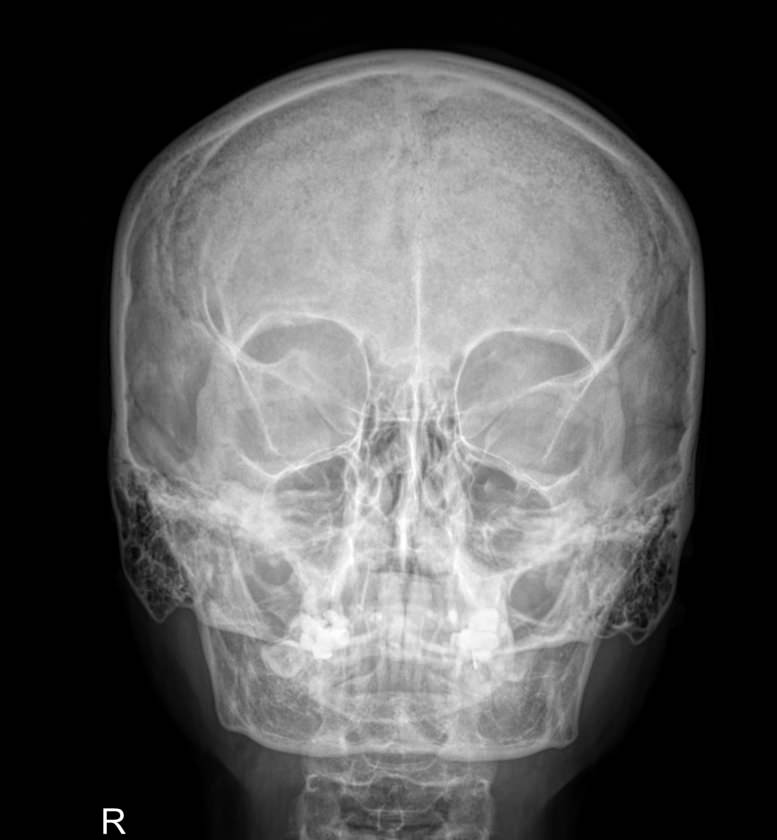

Основное показание к снимку головы ― травма: бытовая, спортивная, в ДТП. Даже если вы посчитали, что отделались ушибом, кости целы и все пройдет само, необходимо обратиться к врачу и удостовериться в целости костей черепа. Тем более, что даже ушиб негативно сказывается на состоянии головного мозга и других органов.

Свежей травме соответствуют следующие симптомы:

• Боль по всей голове, а не только в месте удара;

• Боль при повороте головы;

• Боль при жевании;

• Асимметрия лица или черепа;

• Синяки вокруг глаз;

• Головокружение;

• Тошнота до рвоты;

• Кровотечение и слизетечение из носа и ушей

• Тремор (дрожь) пальцев, ощущение дрожи внутри тела;

• Резкое полное или частичное падение зрения;

• Признаки поражения черепно-мозговых нервов.

Рентгенография требуется также при подозрении на патологию гипофиза, в эндокринной, неврологической и ЛОР-практике. Симптоматика при этом будет соответствовать пораженному органу. Общим симптомом является боль. При врожденных аномалиях развития черепной коробки на первый план выходят именно неврологические признаки.